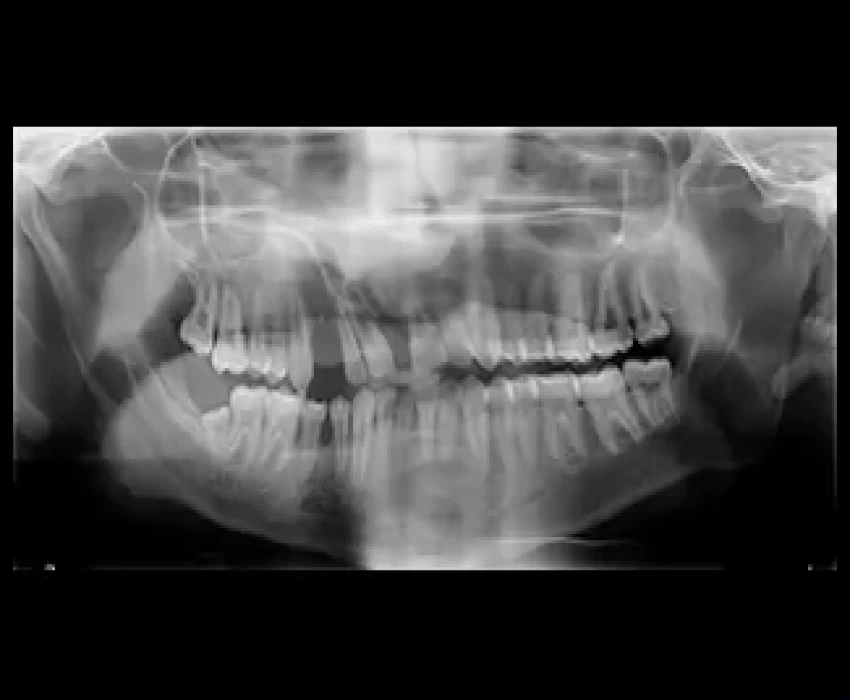

Following investigations were carried out

Radiographs